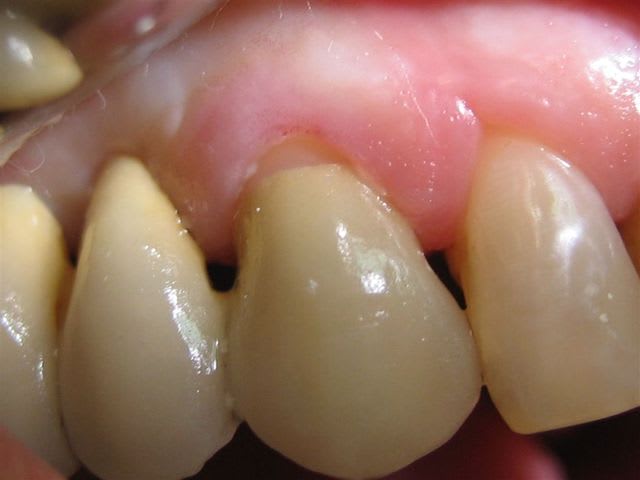

Je ne comprends pas Je Ris,ta taille est parfaite,pourquoi l'épaulement n'est pas complétement recouvert? artefact?

... le congé est localement légèrement sus-gingival.

On ne gagne rien à être juxta ou sous gingival au niveau de la légère récession; au contraire, moins on y touche, mieux ça vaut.